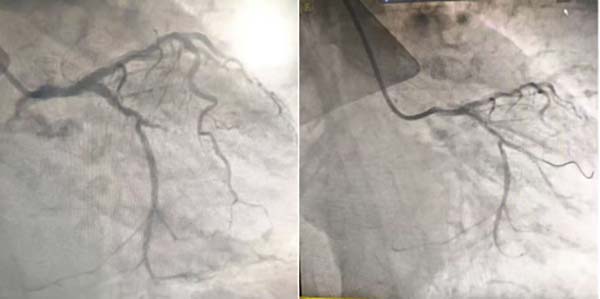

手术室内,一场与时间的赛跑紧张展开。心血管内科包恩泽主任亲自主刀,配台的梁超主治医师和于皓南住院医师各司其职、默契协作。造影结果显示,患者第三钝圆支血管完全闭塞,正是此次心梗的关键病因。凭借丰富的临床经验与规范的操作技艺,医生小心翼翼操控器械通过狭窄病变段,考虑到患者高龄、身体耐受度有限,团队优先采用“介入无植入”的微创方案——通过药物球囊对闭塞血管进行扩张治疗。随着操作完成,原本堵塞的血管瞬间恢复通畅,心肌供血及时复苏,整个手术历时仅30分钟,全程出血少、创伤小,成功为患者打通“生命通道”。